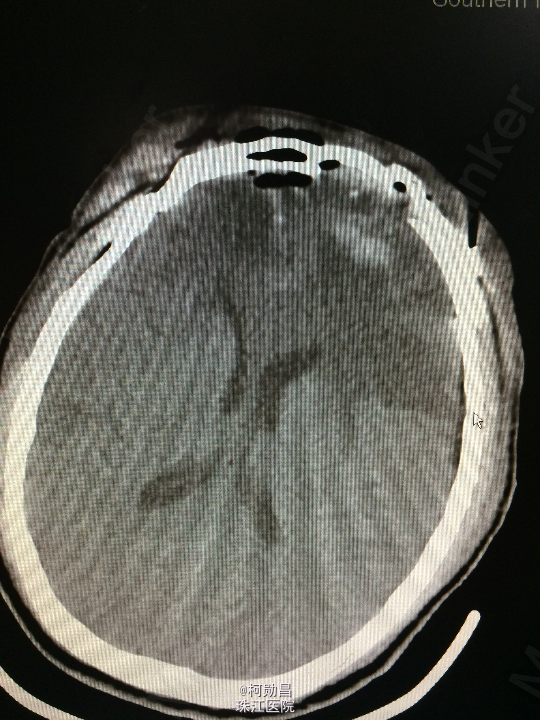

主诉:头痛伴左眼视力下降半年 病史:患者46岁男性,缘于半年前无明显诱因出现头痛,当时未予特殊处理,后症状进行性加重,并发左眼视力下降,于当地医院行头颅CT及MR检查提示颅内占位,为进一步治疗而入我院。 既往病史:5年前曾患鼻咽癌

查体:神志清楚,对答流利,左侧眼裂变小,左侧瞳孔散大,直径4mm,对光反射迟钝,左眼视力下降。右侧正常。 辅助检查:头颅MR提示前颅底筛沟通病变

诊断:鼻咽癌脑转移 处理:全麻下行颅筛沟通占位切除术,术后病理提示:鼻咽非角化鼻咽癌脑转移